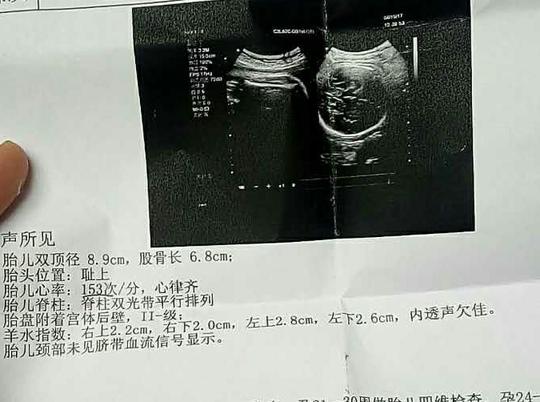

但都没有怀孕.第三个月自己决定做造影.

什么情况下需要做输卵管造影

什么情况需要做输卵管造影

跟大家分享一下我的输卵管造影经历

哪些人需要做输卵管造影?

姐妹们没有怀上,一定做个造影看看输卵管是否畅通.

4步讲解输卵管造影检查过程

输卵管造影不要随便做输卵管造影注意事项

输卵管造影2月19日做的造影2月20

备孕检查做输卵管造影疼吗影响输卵管造影疼痛的因素

不孕,做了造影疑似宫腔粘连了帮忙看下

输卵管造影很疼吗?是怎么做的?

做输卵管造影前后,该需要注意什么?

做个输卵管造影能检查还能治疗?它有什么神奇之处?

输卵管造影检查注意事项

做输卵造影要做什么检查

超生输卵管造影费用图片合集